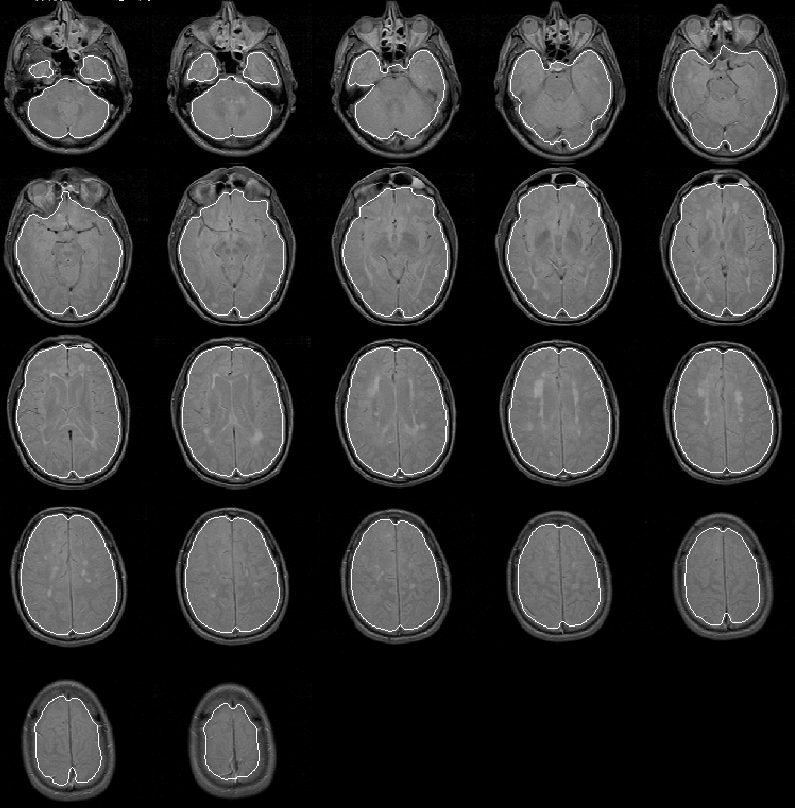

The initial brain mask for Data Set 1, produced by the Generate Initial Brain Mask process, is overlaid on the PD-weighted MR volume in Figure 8.11. Slice 7 is enlarged in Figure 8.12.

Figure 8.11: The initial brain mask for MRI Data Set 1 overlaid on the PD-weighted scan.

The mask apparently identifies all brain tissue regions. Its boundary falls consistently close to, and inside, the intracranial boundary. The initial brain mask should be an ideal seed for the Generate Final Brain Mask process which uses the active contour model algorithm with balloon forces to push the mask boundary outward.